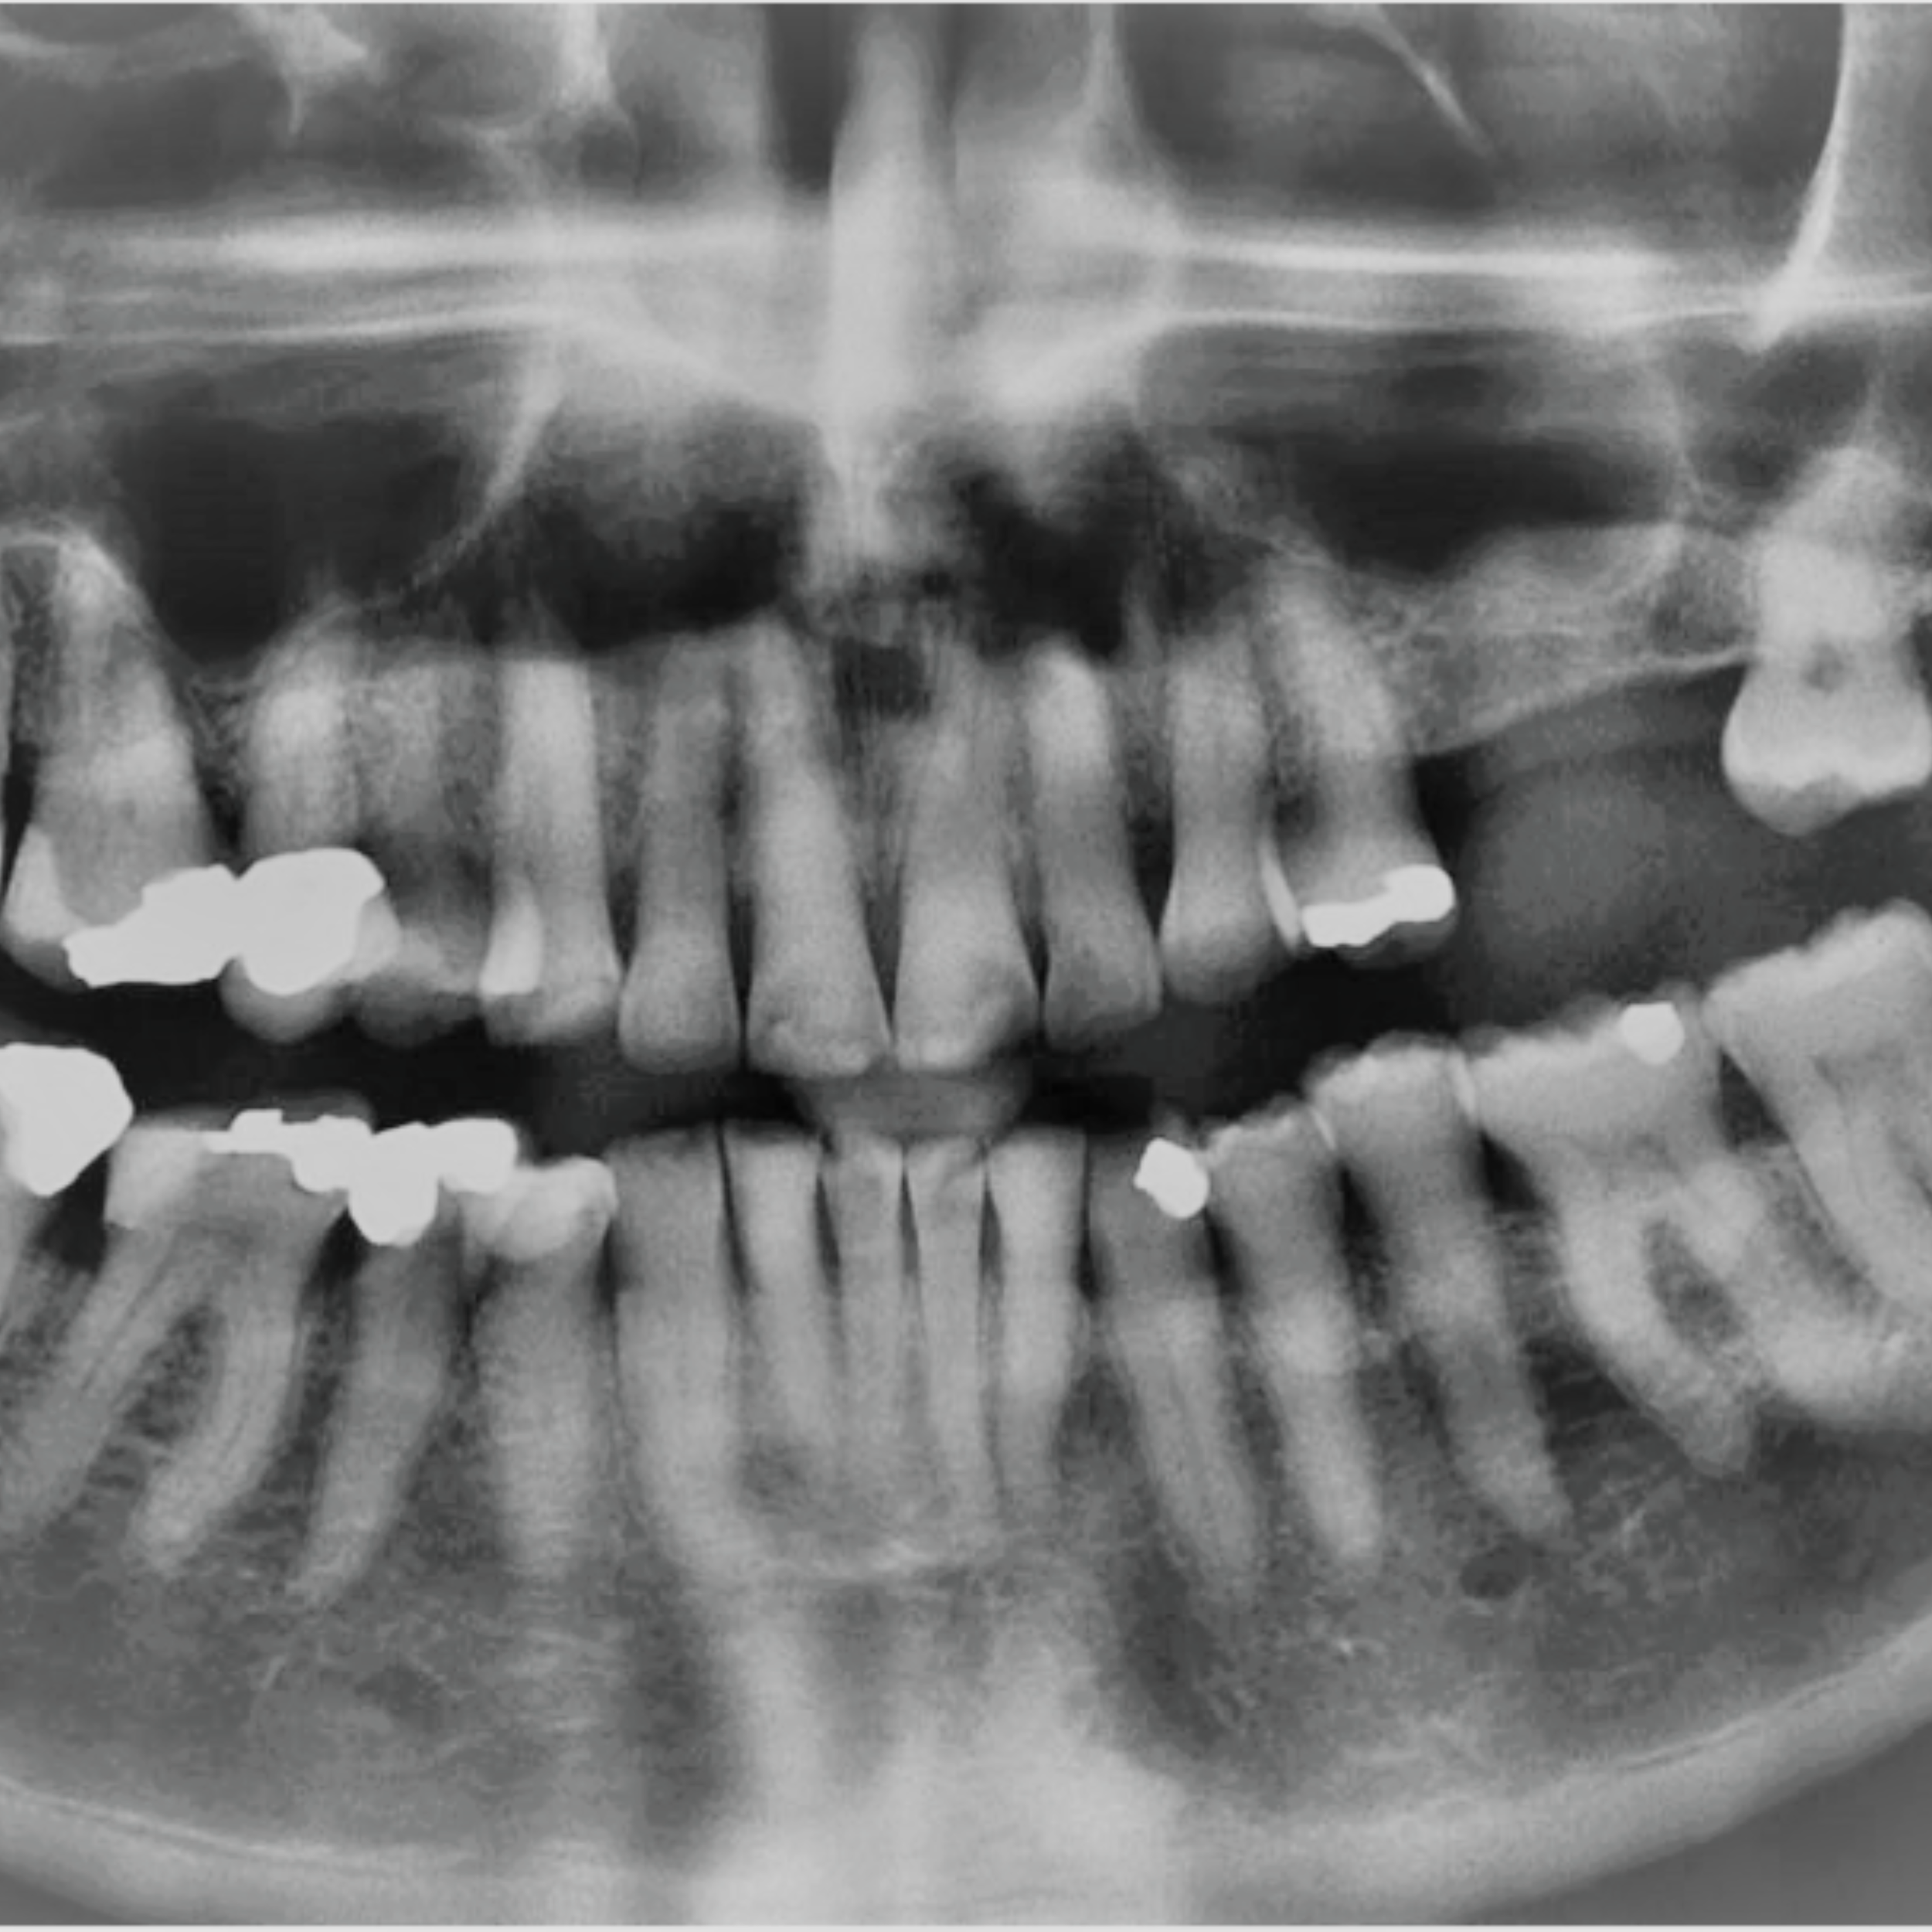

Complete Maxillary Implant-Supported Bridge Case